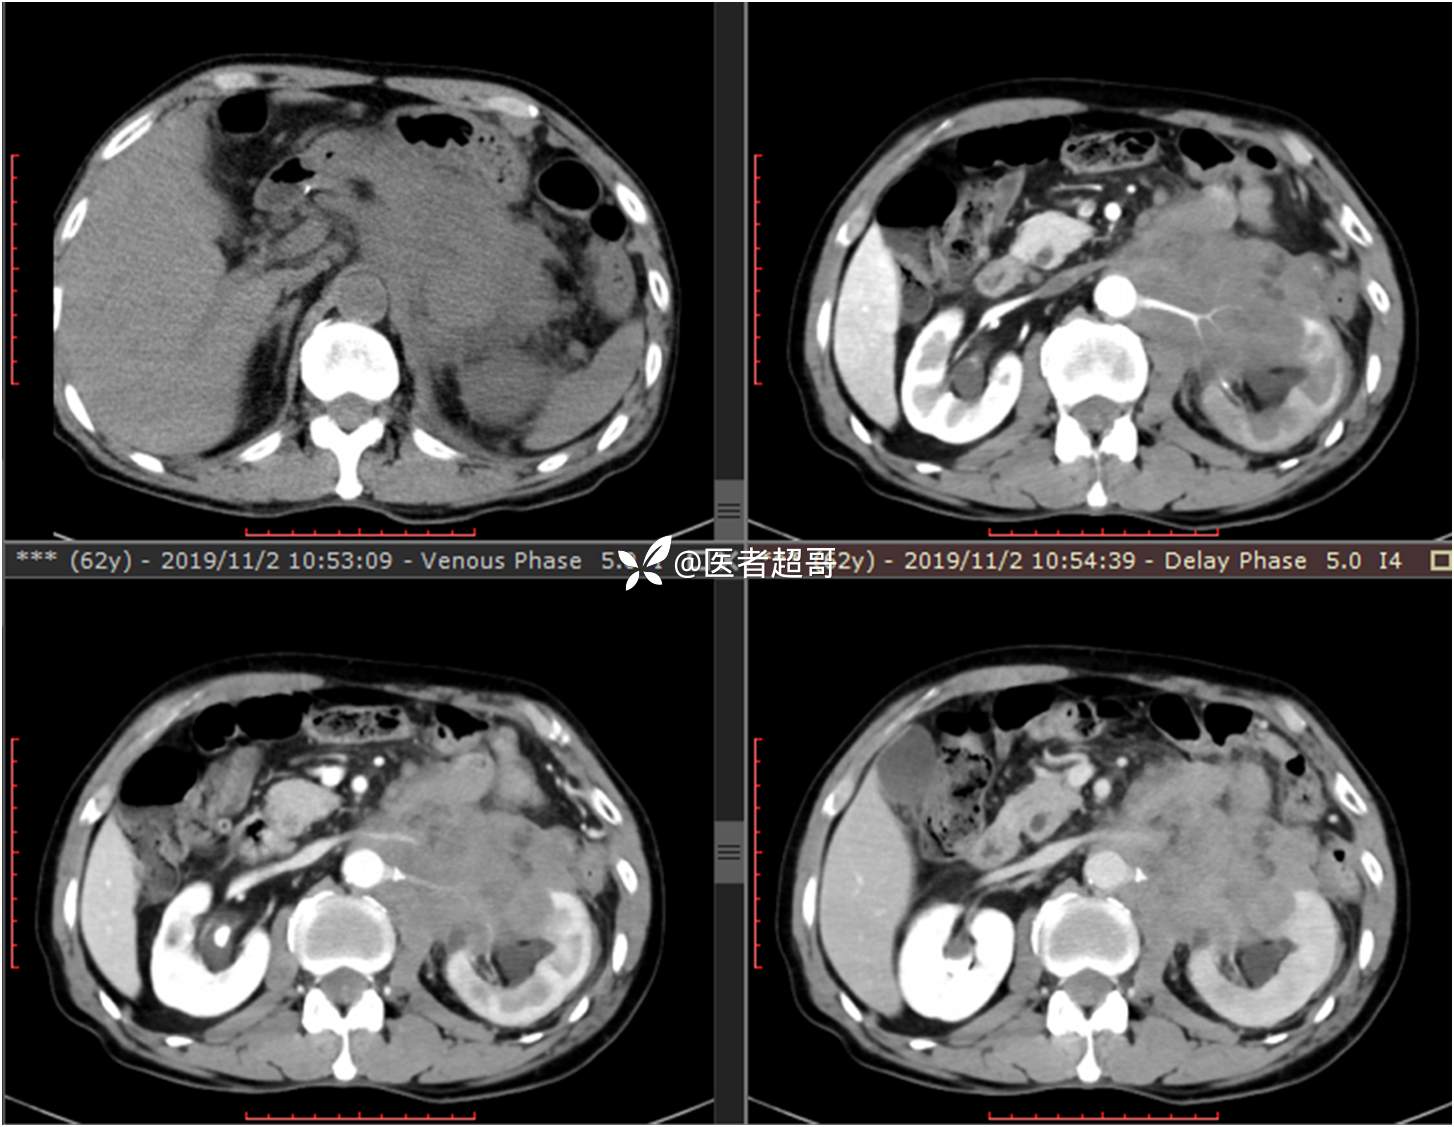

现病史:患者于1月前无明显原因及诱因出现左上腹部疼痛,为间断性疼痛,无恶心、呕吐,无寒战、高热,无腹胀、腹泻等伴随症状,在外未行特殊处理,患者于1周前自觉疼痛加重,为求诊治患者曾就诊于市东城医院,行全腹部强化CT提示:左肾上腺区肿块,符合恶性肿瘤侵犯左肾、胰腺及腹膜后大血管CT表现,行保守治疗,症状缓解,今患者为求进一步诊治,来我院就诊,行腹膜后占位穿刺活检病理提示:(腹膜后占位穿刺)小细胞背景内见细胞浆红染的神经节样细胞,建议到病理科加做免疫组化进一步明确诊断,遂以“腹膜后肿物”收入院,患者自发病以来,神志清,精神可,饮食、睡眠差,大小便正常,体重未见明显改变。